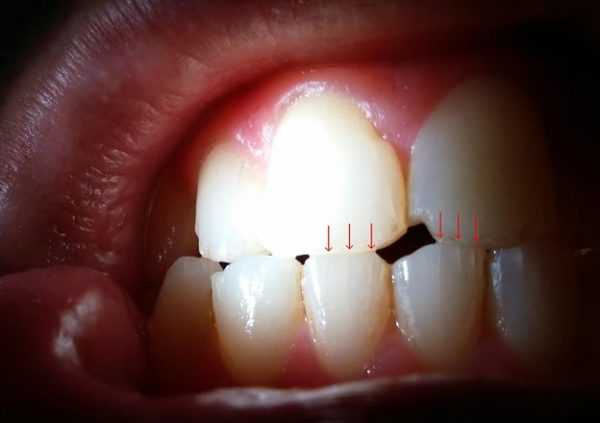

خطوط ریز چگونه به نظر می رسند؟

خطوط ریز مانند ترک های ریز مویی شکل روی مینای دندان های شما به نظر می رسند. آنها به صورت خطوط عمودی کم عمق و مستقیم ظاهر می شوند.

گاهی اوقات ممکن است خطوط ریز به رنگ های زرد، خاکستری یا قهوه ای به نظر برسند. در موارد دیگر، آنها شفاف هستند و به سختی قابل توجه هستند (مگر اینکه به دقت نگاه کنید یا دندان ها را خشک کنید).

اگر نوری را با زاویه ای خاص روی دندان های خود بتابانید، به راحتی می توانید خطوط ریز را مشاهده کنید. نور از سطوح ترک های مویی منعکس خواهد شد.